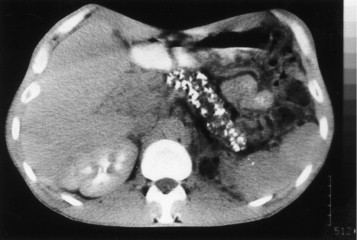

A 42-year-old man comes to the physician because of severe epigastric pain for a week. The pain is constant and he describes it as 6 out of 10 in intensity. The pain radiates to his back and is worse after meals. He has had several episodes of nausea and vomiting during this period. He has taken ibuprofen for multiple similar episodes of pain during the past 6 months. He also has had a 5.4-kg (12-lb) weight loss over the past 4 months. He has a 12-year history of drinking 3 to 4 pints of rum daily. He has been hospitalized three times for severe abdominal pain in the past 3 years. He appears ill. His temperature is 37°C (98.6°F), pulse is 87/min, and blood pressure is 110/70 mm Hg. There is severe epigastric tenderness to palpation. Bowel sounds are normal. Cardiopulmonary examination shows no abnormalities. Laboratory studies show: Hemoglobin 13.6 g/dL Leukocyte count 7,800/mm3 Serum Glucose 106 mg/dL Creatinine 1.1 mg/dL Amylase 150 U/L A CT of the abdomen is shown. Which of the following is the most appropriate long-term management for this patient?

Explanation: ***Pancreatic enzyme therapy*** - This patient likely has **chronic pancreatitis** due to long-term alcohol abuse, presenting with severe epigastric pain, weight loss, and recurrent episodes. **Pancreatic enzyme replacement therapy (PERT)** helps in managing malabsorption and pain by reducing pancreatic stimulation. - While amylase is only slightly elevated (150 U/L), this is typical in chronic pancreatitis where extensive glandular destruction prevents dramatic enzyme elevation seen in acute pancreatitis. The abdominal CT would likely show calcifications or ductal dilation, further supporting the diagnosis and the need for enzyme support due to **exocrine insufficiency.** *Whipple procedure* - The **Whipple procedure** (pancreaticoduodenectomy) is a complex surgical intervention primarily performed for **pancreatic head tumors** or severe, intractable chronic pancreatitis not amenable to less invasive treatments. - This patient's symptoms, while severe, do not immediately indicate a need for such aggressive surgery, and other medical managements should be attempted first. *Endoscopic stent placement* - **Endoscopic stent placement** is typically used to relieve **biliary obstruction** or **pancreatic duct strictures** that cause pain or cholangitis in chronic pancreatitis. - While it might be considered for specific ductal complications, it is not the initial long-term management for the diverse symptoms of chronic pancreatitis, especially **exocrine insufficiency**. *Celiac ganglion block* - A **celiac ganglion block** provides temporary pain relief for severe abdominal pain, particularly in conditions like **chronic pancreatitis** or **pancreatic cancer**, by interrupting nerve signals. - It is a **palliative measure** for pain control and does not address the underlying **exocrine insufficiency** or disease progression, making it not a long-term comprehensive management strategy. *Gluten-free diet* - A **gluten-free diet** is the primary treatment for **celiac disease**, an autoimmune disorder affecting the small intestine. - There is no clinical indication or laboratory finding in this patient's presentation (e.g., diarrhea, positive celiac serology) to suggest celiac disease as the cause of his symptoms or to warrant a gluten-free diet.